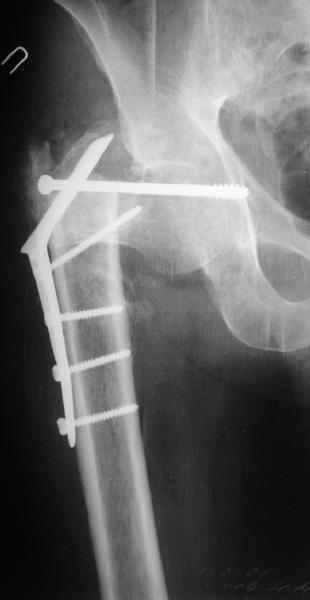

Leonid Solomin 03 Март 2009, 22:07

Уважаемый Попов Виктор!

Возможно, пример (в приложении) поможет Вам определиться с выбором тактики лечения (у нашего пациента, кроме тугого ложного сустава вертельной области, сложная деформация н/3 бедренной кости; т.к. это не имеет значения к обсуждаемой теме - оставил "за кадром"). Как Вы видите, мы в данном случае не вводили чрескостные элементы в зону установки имплантата. При отказе от наложения опоры на таз (кстати, она не обязательно может быть громоздкая спицевая; арки со стержнями-шурупами, введенными в крыло подвздошной вполне достаточно) "не удивляйтесь", если опора со стержнями-шурупами, введенными в вертельной области в скором времени дестабилизируется, возникнет воспаление мягких тканей у чрескостных элементов. Такая опора "имеет на это право": нагрузка конечности от вершины дистального фрагмента до кончиков пальцев ляжет на нее. А двух-трех введенных рядом стержней-шурупов, как их не разноси от фронтальной плоскости, в данном

случае явно недостаточно для адекватной фиксации. + для того, чтобы выбрать оптимальные чрескостные элементы для промежуточной и дистальной опор, можете воспользоваться атласом

В приложении пример пациента, близкого по картине к тому, что представил Виктор (варус и смещение периферического отломка на поперечник кзади). Сделали как раз то, что Виктор исходно намеревался - аппаратная коррекция и затем гамма.